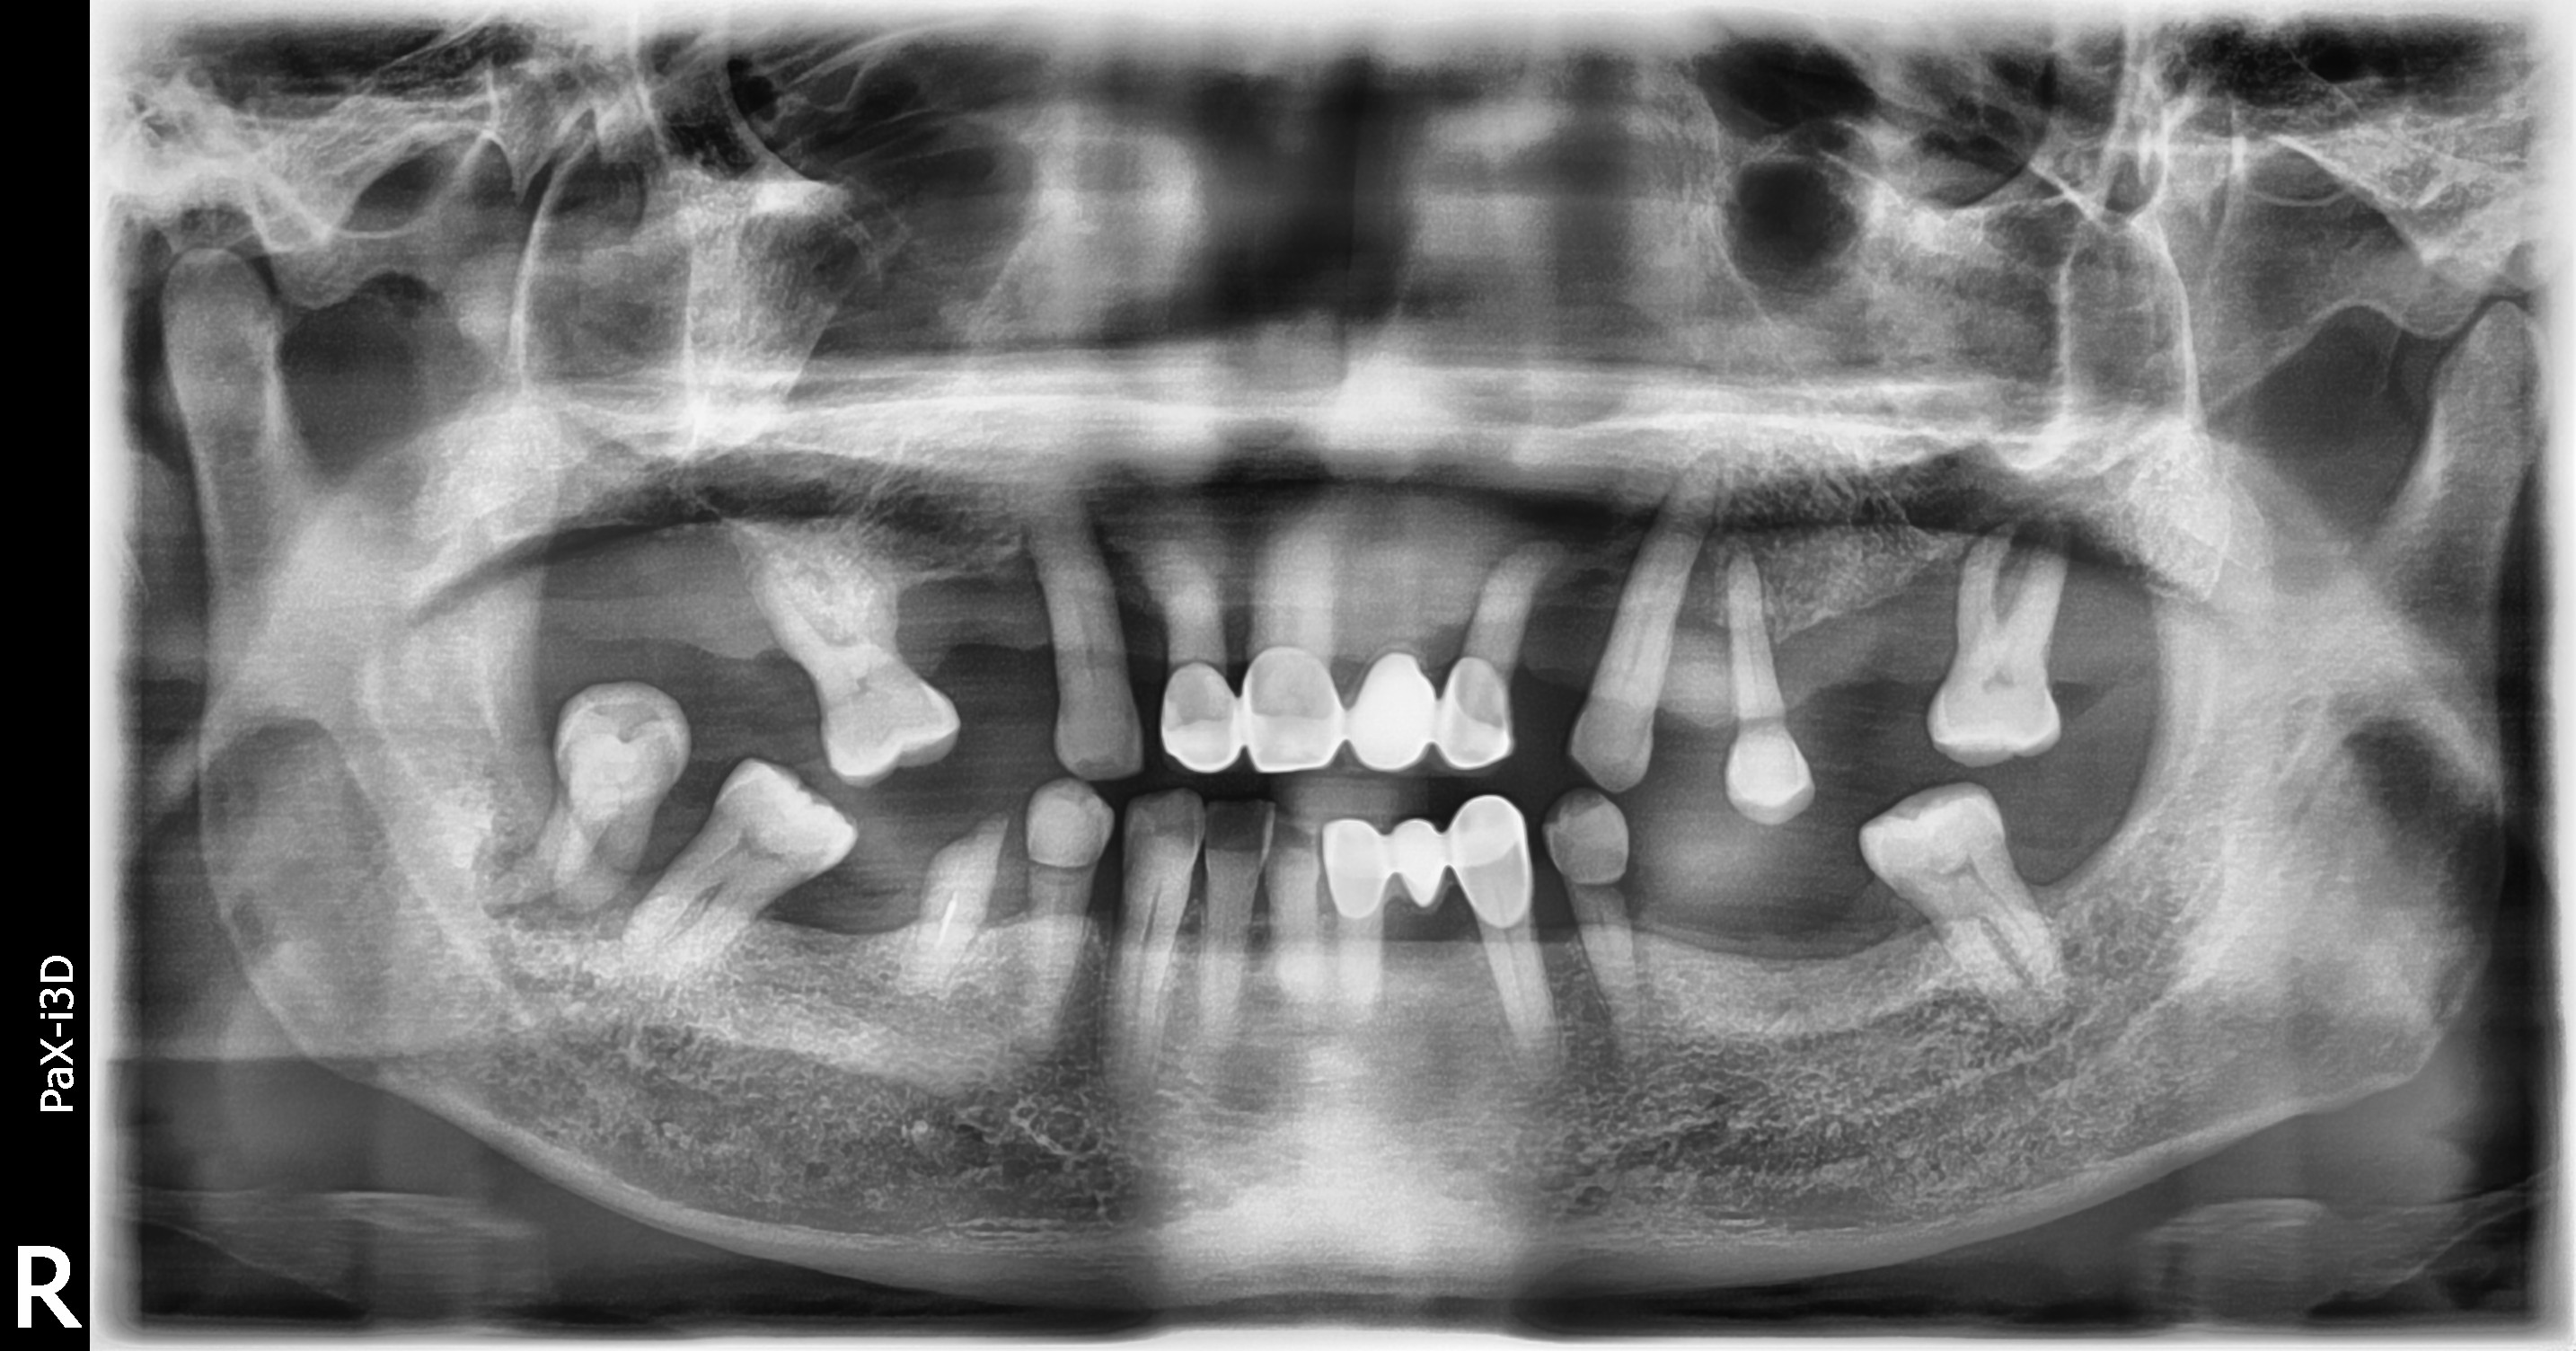

BEFOREAFTERBEFOREAFTER(식립)AFTER(착용)

전체틀니

임플란트 틀니

부분틀니